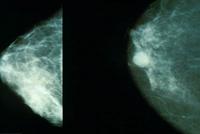

July 26, 2011 – Due to the high incidence of breast cancer in the United States and the potential to reduce deaths from it when caught early, The American College of Obstetricians and Gynecologists (ACOG) issued new breast cancer screening guidelines that recommend mammography screening be offered annually to women beginning at age 40. Previous ACOG guidelines recommended mammograms every one to two years starting at age 40 and annually beginning at age 50.

According to Jennifer Griffin, M.D., MPH, who co-authored ACOG guidelines, the change in mammography screening for women beginning at age 40 is based on three factors: the incidence of breast cancer, the sojourn time for breast cancer growth and the potential to reduce the number of deaths from it. The time period between when a breast cancer may be detected by a mammogram while it is very small and before it grows big enough to become symptomatic is known as the sojourn time. Although the sojourn time of individual cancers can vary, the greatest predictor is age. Women ages 40-49 have the shortest average sojourn time (2-2.4 years), while women ages 70-74 have the longest average sojourn time (4-4.1 years).

"Although women in their 40s have a lower overall incidence of breast cancer compared with older women, the window to detect tumors before they become symptomatic is shorter, on average," said Griffin. The five-year survival rate is 98 percent for women whose breast cancer tumors are discovered at their earliest stage, before they are palpable and when they are small and confined to the breast. "If women in their 40s have annual mammograms, there is a better chance of detecting and treating the cancer before it has time to spread than if they wait two years between mammograms."